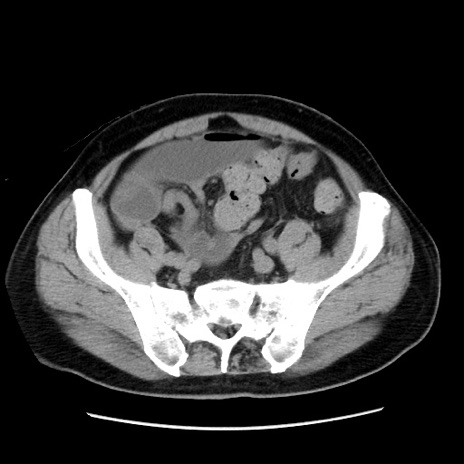

症例16(横断像)

【症例】 70歳代男性

【主訴】 腹痛、嘔吐

【現病歴】 約1ヶ月前より間欠的に腹痛と嘔吐あり、当院消化器内科を受診したところCTで多発する肝臓のLDAを指摘され、精査中であった。以降は消化器症状は安定していたが、2日前より嘔気と腹痛があり、同日より排便・排ガスが消失した。改善認めず、 本日、救急外来を受診した。

【既往歴】 大腸ポリープ切除後。

【身体所見】意識清明・会話良好、BT 36.3℃、BP 127/80mmHg、 P 80bpm、腹部:膨満あり、平坦・軟、上腹部正中および下腹部正中に圧痛あり、反跳痛なし、筋性防御なし。

【データ】WBC 7200、CRP 0.77